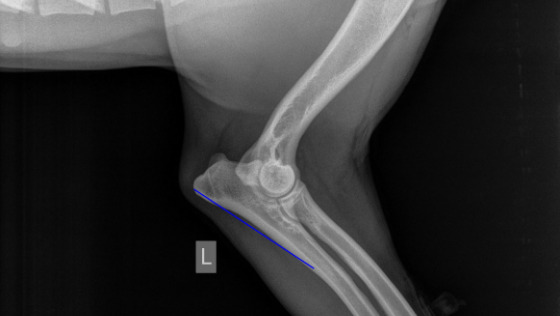

Zarówno artroskopia, jak i stabilizacja łokcia udały się doskonale, wszystko poszło gładko i bez komplikacji :)